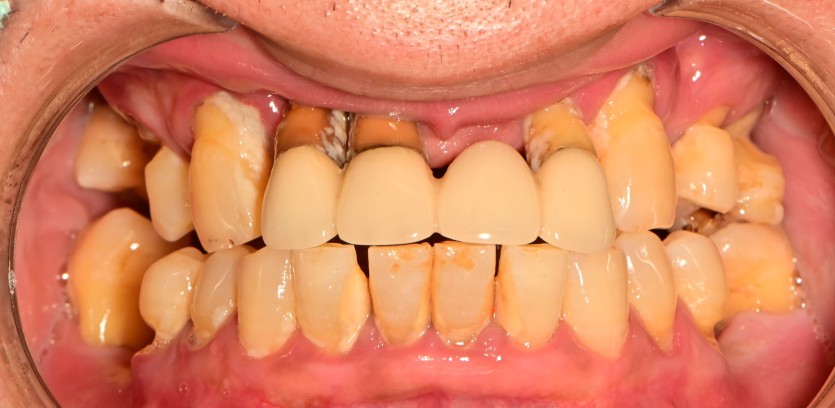

상악 풀아치 임플란트 증례입니다.

6개의 임플란트로 완성하였습니다.